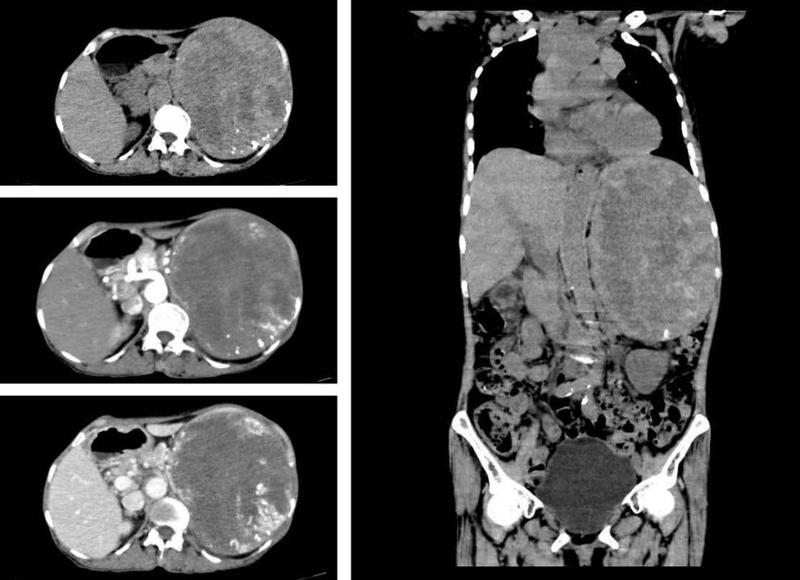

来到南方医科大学中西医结合医院时,陈阿婆左腹鼓起的大包块已越来越明显,在她消瘦的身体上显得十分突兀。通过检查发现脾脏体积异常增大,约为15cm*10cm,胃、胰腺、左肾因此受压移位,造成身体不适。

全脾切除后,测量体积为20*16*7.5cm,而正常脾脏的大小仅为10*6*3到12*8*4cm左右。术后病理诊断发现全脾大片状坏死周围见血管增生,间质较多淋巴细胞、浆细胞浸润,结合HE形态及免疫组化结果,诊断为“脾硬化性血管瘤样结节性转化”。